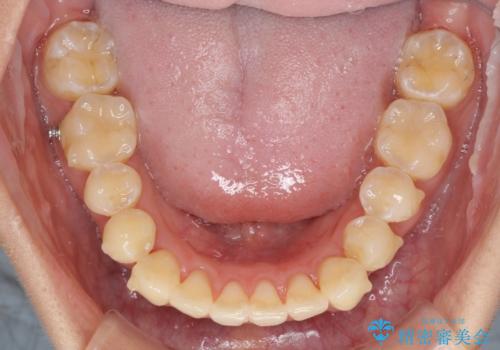

八重歯の再矯正 インビザラインでストレスなく矯正治療

- 学生の頃に矯正治療を行ったものの、保定を怠けてしまったことによる後戻りを気にして来院された患者様です。

根管治療が必要な歯があったため、矯正治療前に根管治療を行い、その後はインビザラインにより矯正治療を行うこととしました。

下顎の八重歯が上顎歯列に収まる過程で咬みにくさがありましたが、最終的には、咬み合わせも安定し、きれいに歯列を整えることができました。